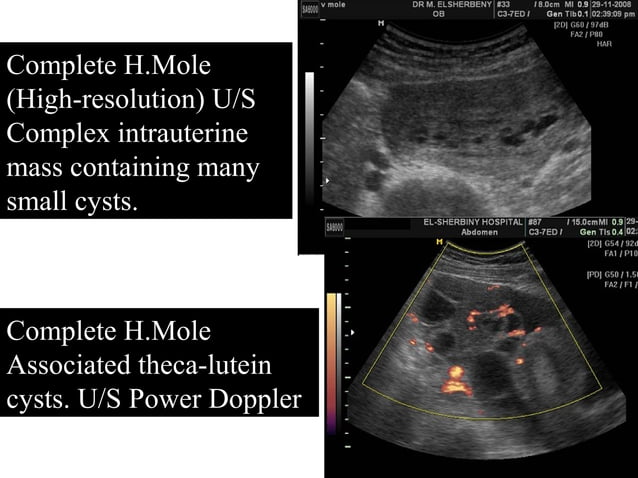

molar pregnancy ultrasound symptoms mole hydatidiform signs fetus causes